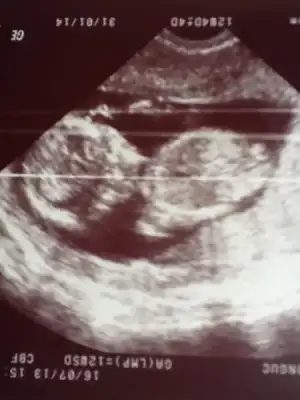

Arkadaslar bızede bı yorumda bulunabılırmısınız 11+4burda ATTACH=CONFIG]754948[/ATTACH]

Eklentiler

Ben yanlışlıkla iki kere yüklemiştim arkadaşlar :) heyecandan ... İlk foto 12+5 2. 11+5 3. De 11+5 diğerleri de aynı zaten